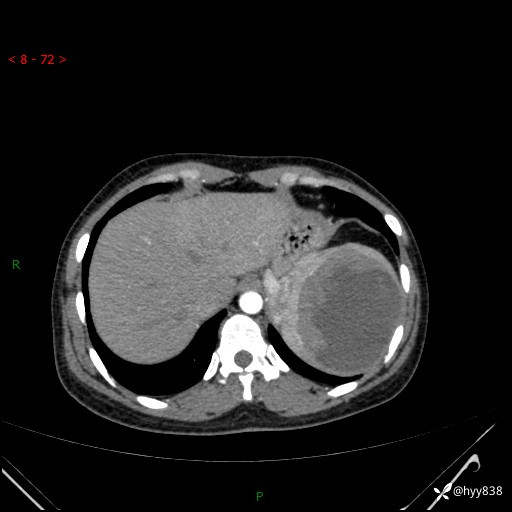

患者性别:男

患者年龄:44岁

主诉:外院超声发现脾脏占位,来我院进一步诊治。

辅助检查:CT

临床诊断:脾脏占位

脾脏CT平扫+增强(动脉期+静脉期)